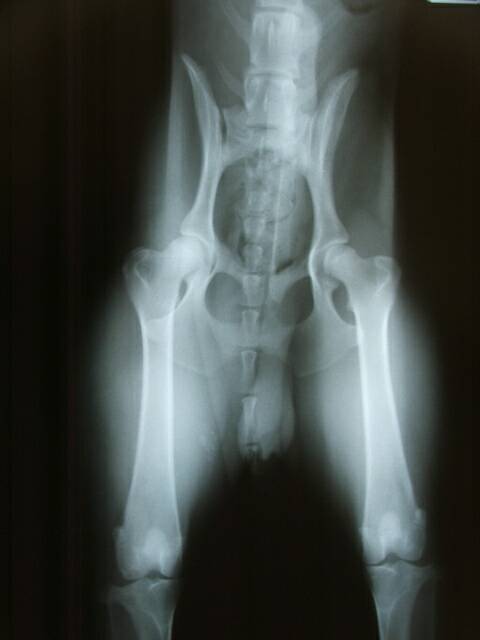

Hips

Hips can be x-rayed by any vet, but results should be evaluated by OFA (Orthopedic Foundation for Animals) or Penn Hip. Proof should be provided.